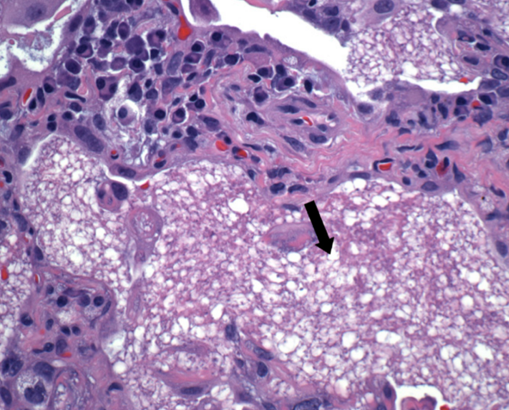

PCP Histology

Histopathologic and cytologic findings in Pneumocystis jirovecii pneumonia (PCP) include eosinophilic foamy alveolar material (arrow in exhibit) and cystic and trophic forms that can be stained with Giemsa or silver (producing a cup-in-saucerappearance with these stains). In addition, PCP is more common in patients with advanced HIV than in transplant patients and would be unlikely in this patient on PCP prophylaxis with trimethoprim-sulfamethoxazole.